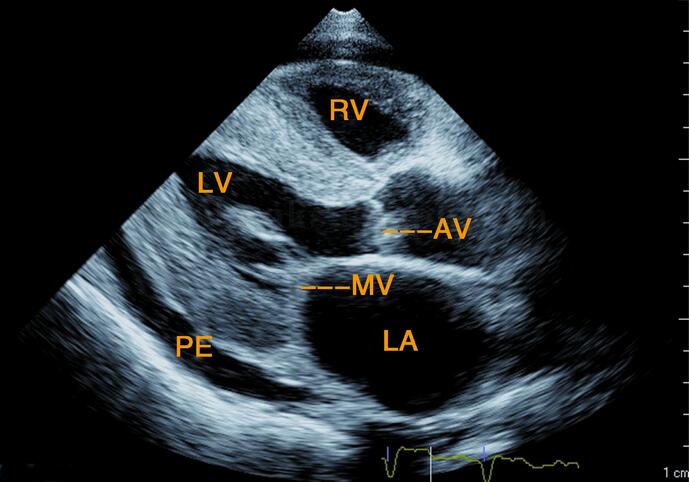

图2‐1‐216 左室长轴切面

左房增大,左室壁弥漫性增厚,回声增强,二尖瓣、主动脉瓣增厚,回声增强,左室后壁后中等量心包积液